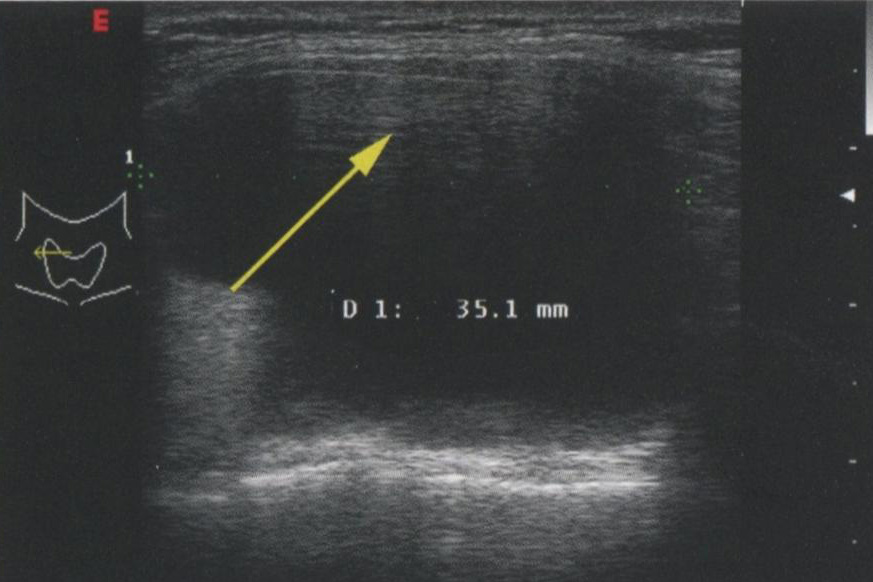

И хотя более высокие частоты дают лучшее разрешение, глубина визуализации с увеличением частоты снижается. В современных УЗ-аппаратах для исследования ЩЖ используется достаточно высокая частота — 16 МГц. Однако при этой частоте исследование можно провести лишь на глубину до 5 см. Визуализация более глубоких структур, как и при УЗИ органов брюшной полости или малого таза, требует более низкой частоты. У тучных пациентов или при исследовании очень глубоких структур для адекватного проникновения луча и визуализации глубоких структур шеи может потребоваться частота 5-7,5 МГц. На рис. 2.22 и рис. 2.23 сравниваются изображения при частоте 7,5 и 13 МГц. Видно, что детализация проксимальных структур при более низкой частоте снижается.

Рис. 2.22. Сравнение изображений, сделанных при частоте в 7,5 и 13 МГц. При использовании датчика с частотой 7,5 МГц узел определяется менее четко, но структуры кзади от него визуализируются лучше. Сравните с рисунком 2.23

Рис. 2.23. Сравнение изображений при частоте 7,5 и 13 МГц. На этом изображении при частоте 13 МГц узел визуализируется намного четче. Сравните с рисунком 2.22